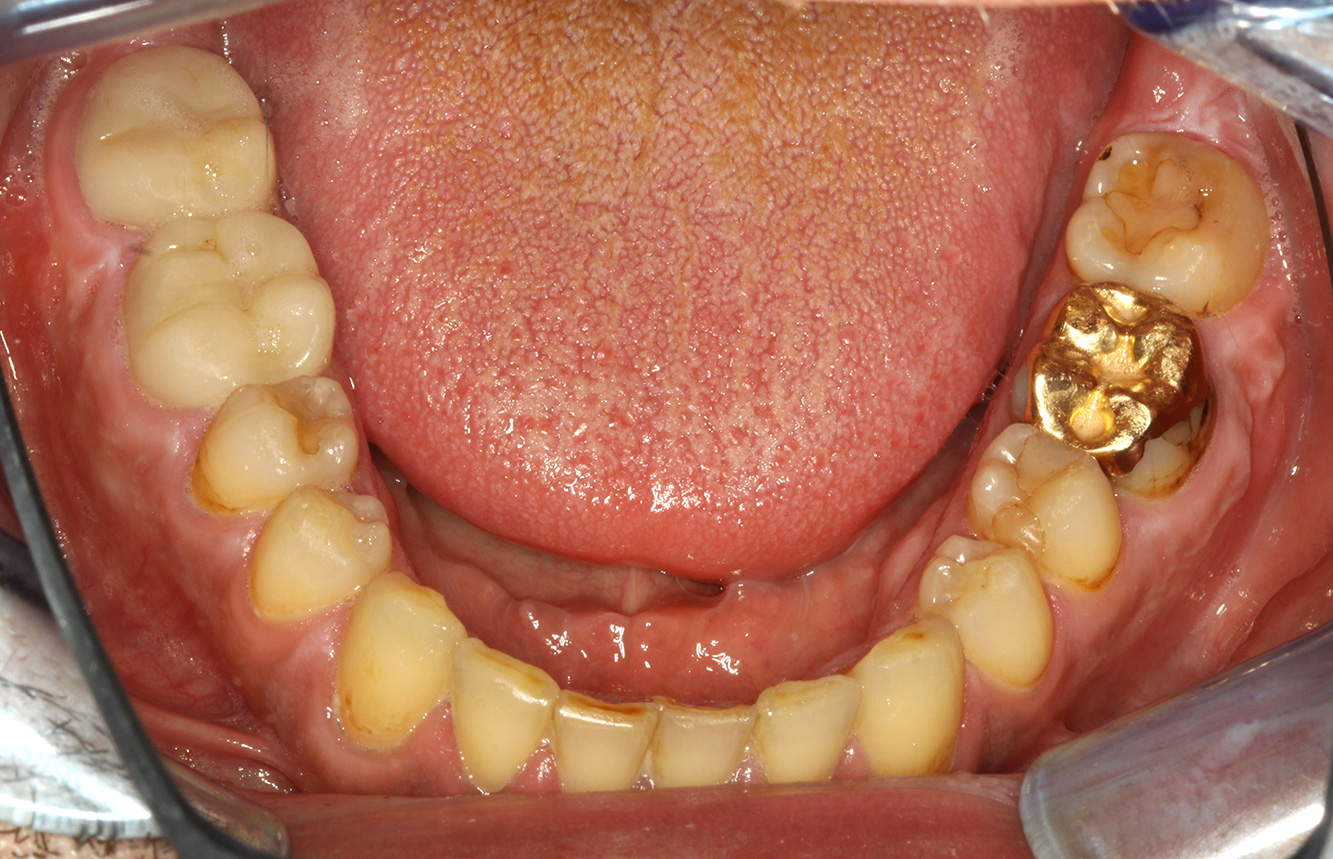

Ein 71-jähriger Patient mit Z.n. Nierentransplantation und Hypertonie (Bluthochdruck) stellt sich vor. Bedingt durch die Krankengeschichte ist eine Dauermedikation mit Cyclosporin, zur Unterdrückung der Immunabwehr, und Amlodipin, zur Blutdrucksenkung, erforderlich. Außerdem berichtet der Patient über empfindliches Zahnfleisch und Zahnfleischbluten. Aus mundgesundheitlicher Sicht zeigt sich ein saniertes Gebiss mit acht fehlenden Zähnen, ausgeprägte Gingivawucherungen, eine Parodontitis Stadium II, Grad B mit aktiven Taschen und eine initiale Wurzelkaries an Zahn 22. In der Kariesrisikoabschätzung wird ein mittleres Kariesrisiko (API 60) festgestellt. Für die Prophylaxesitzung lassen sich folgende Behandlungsempfehlungen ableiten. mehr Infos